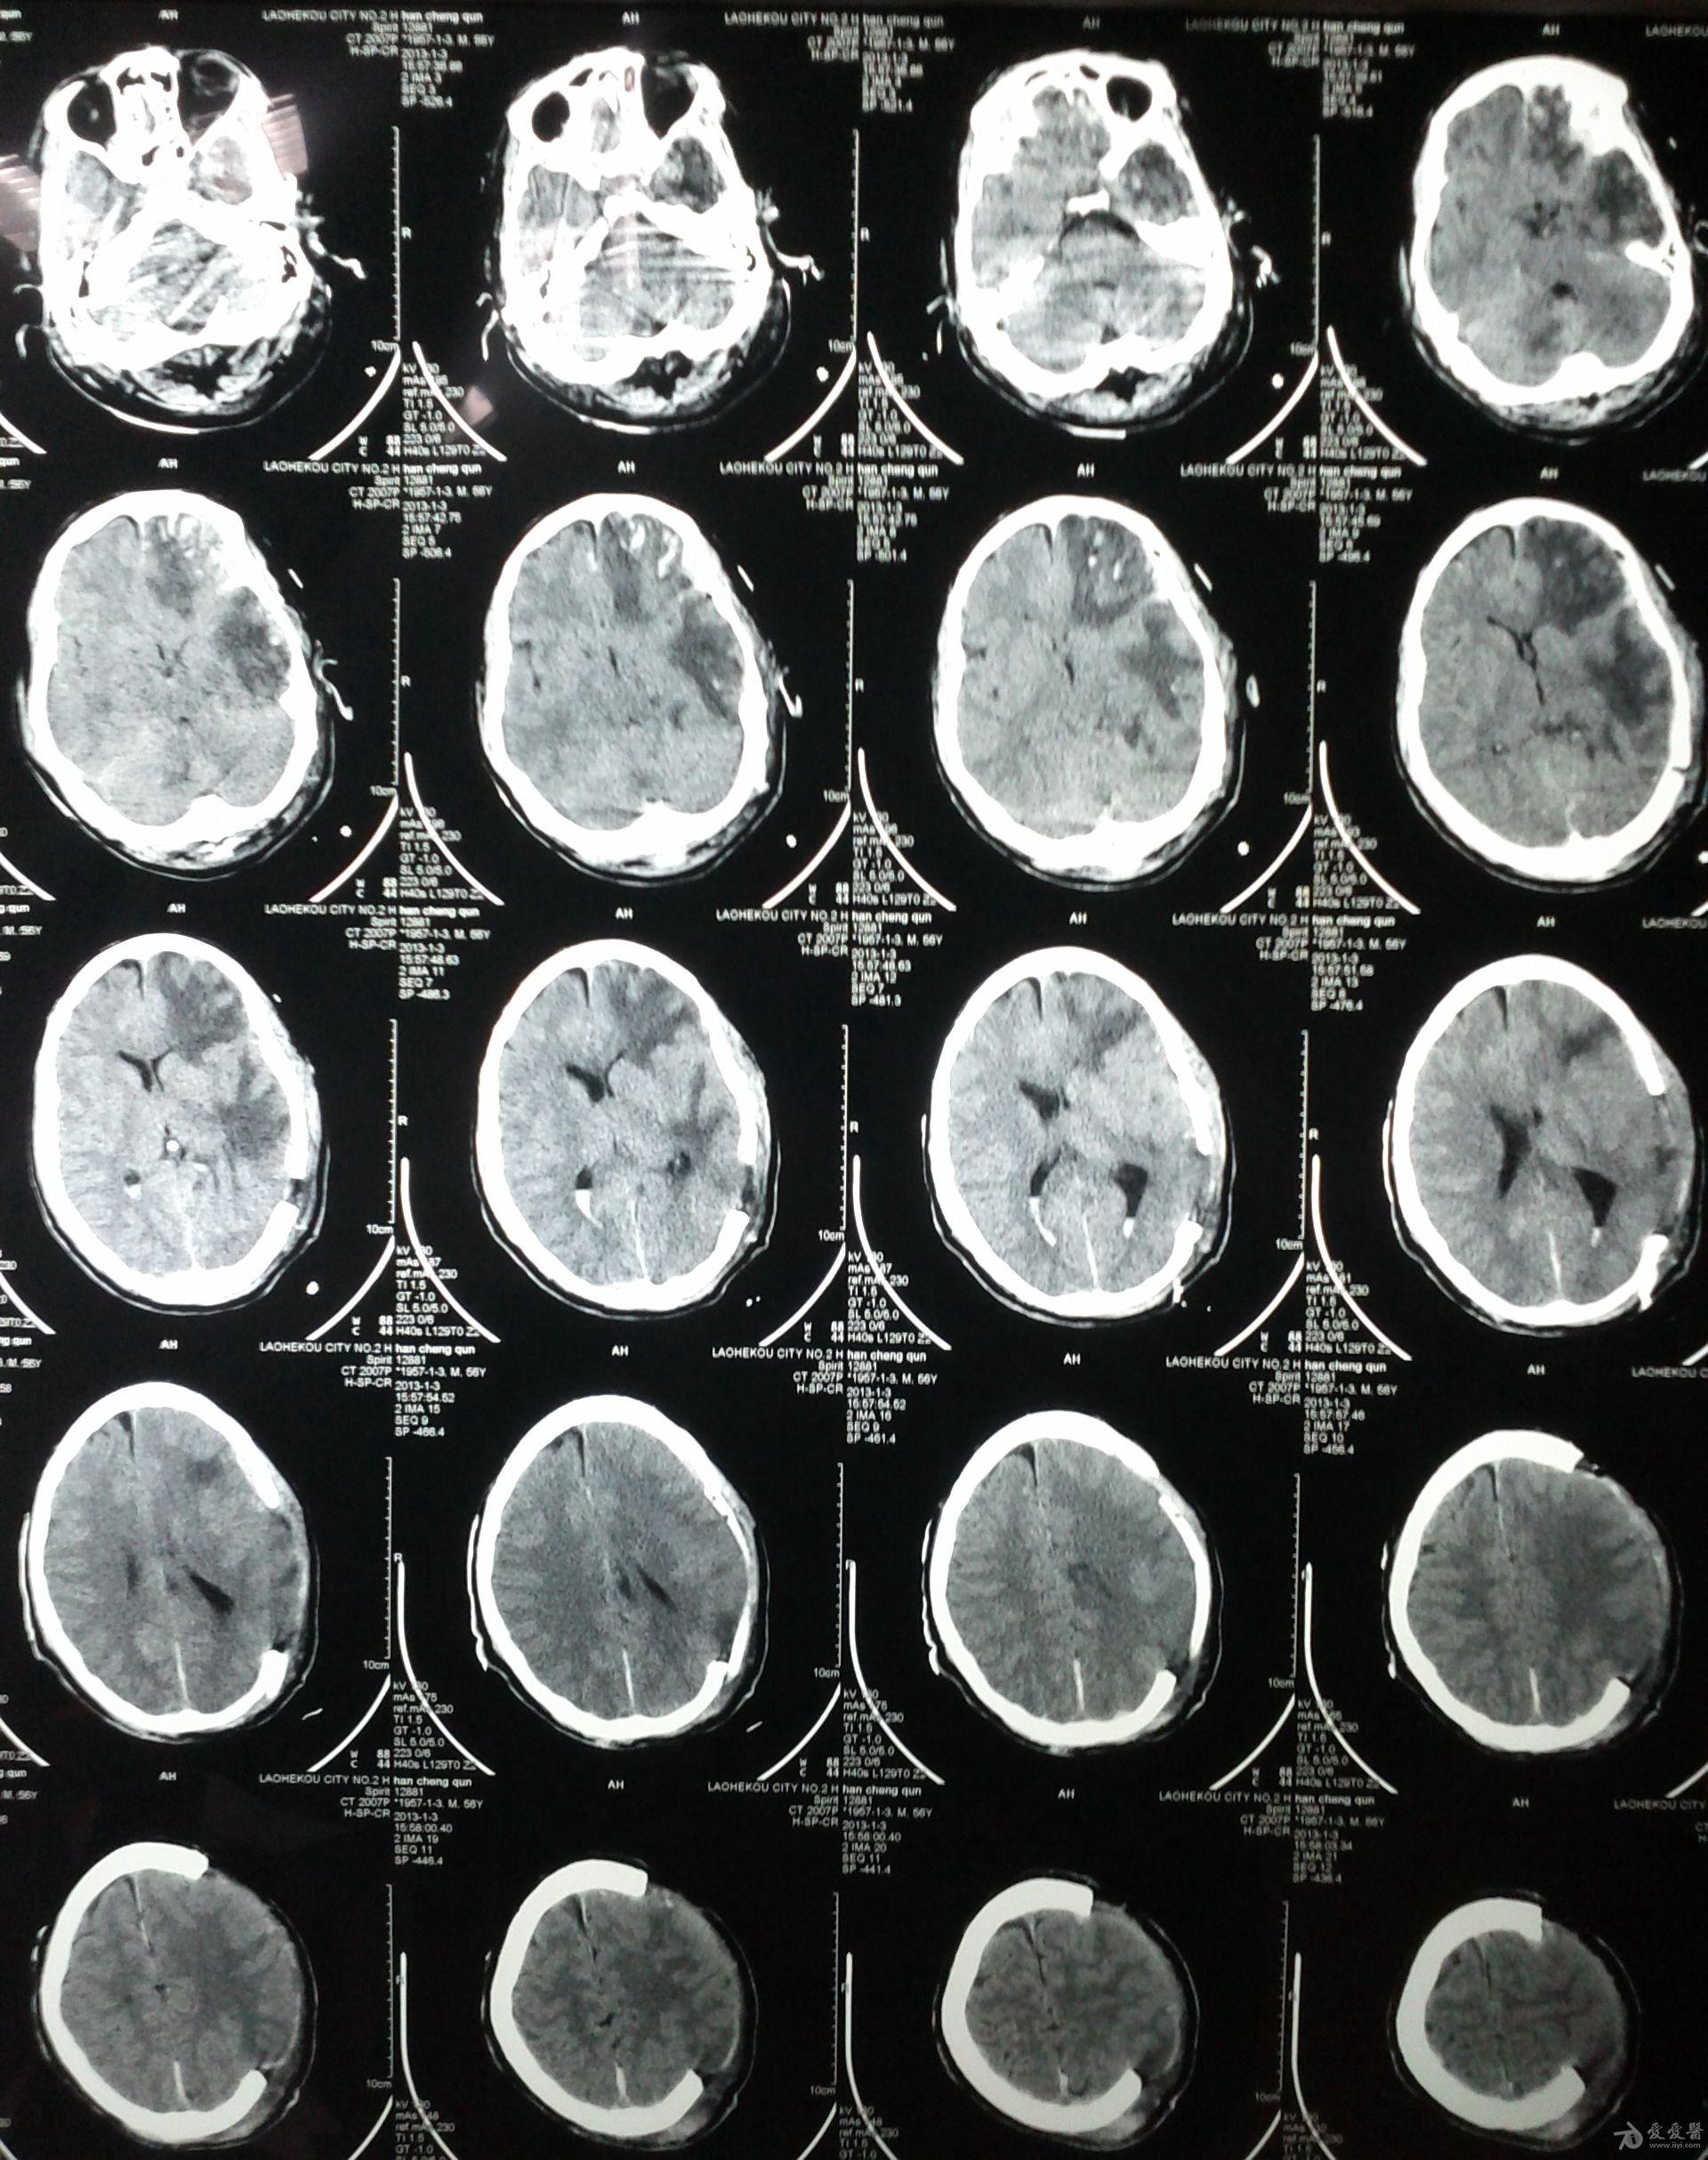

分享重型颅脑损伤双侧去骨瓣病例1则

图片尺寸4032x3024